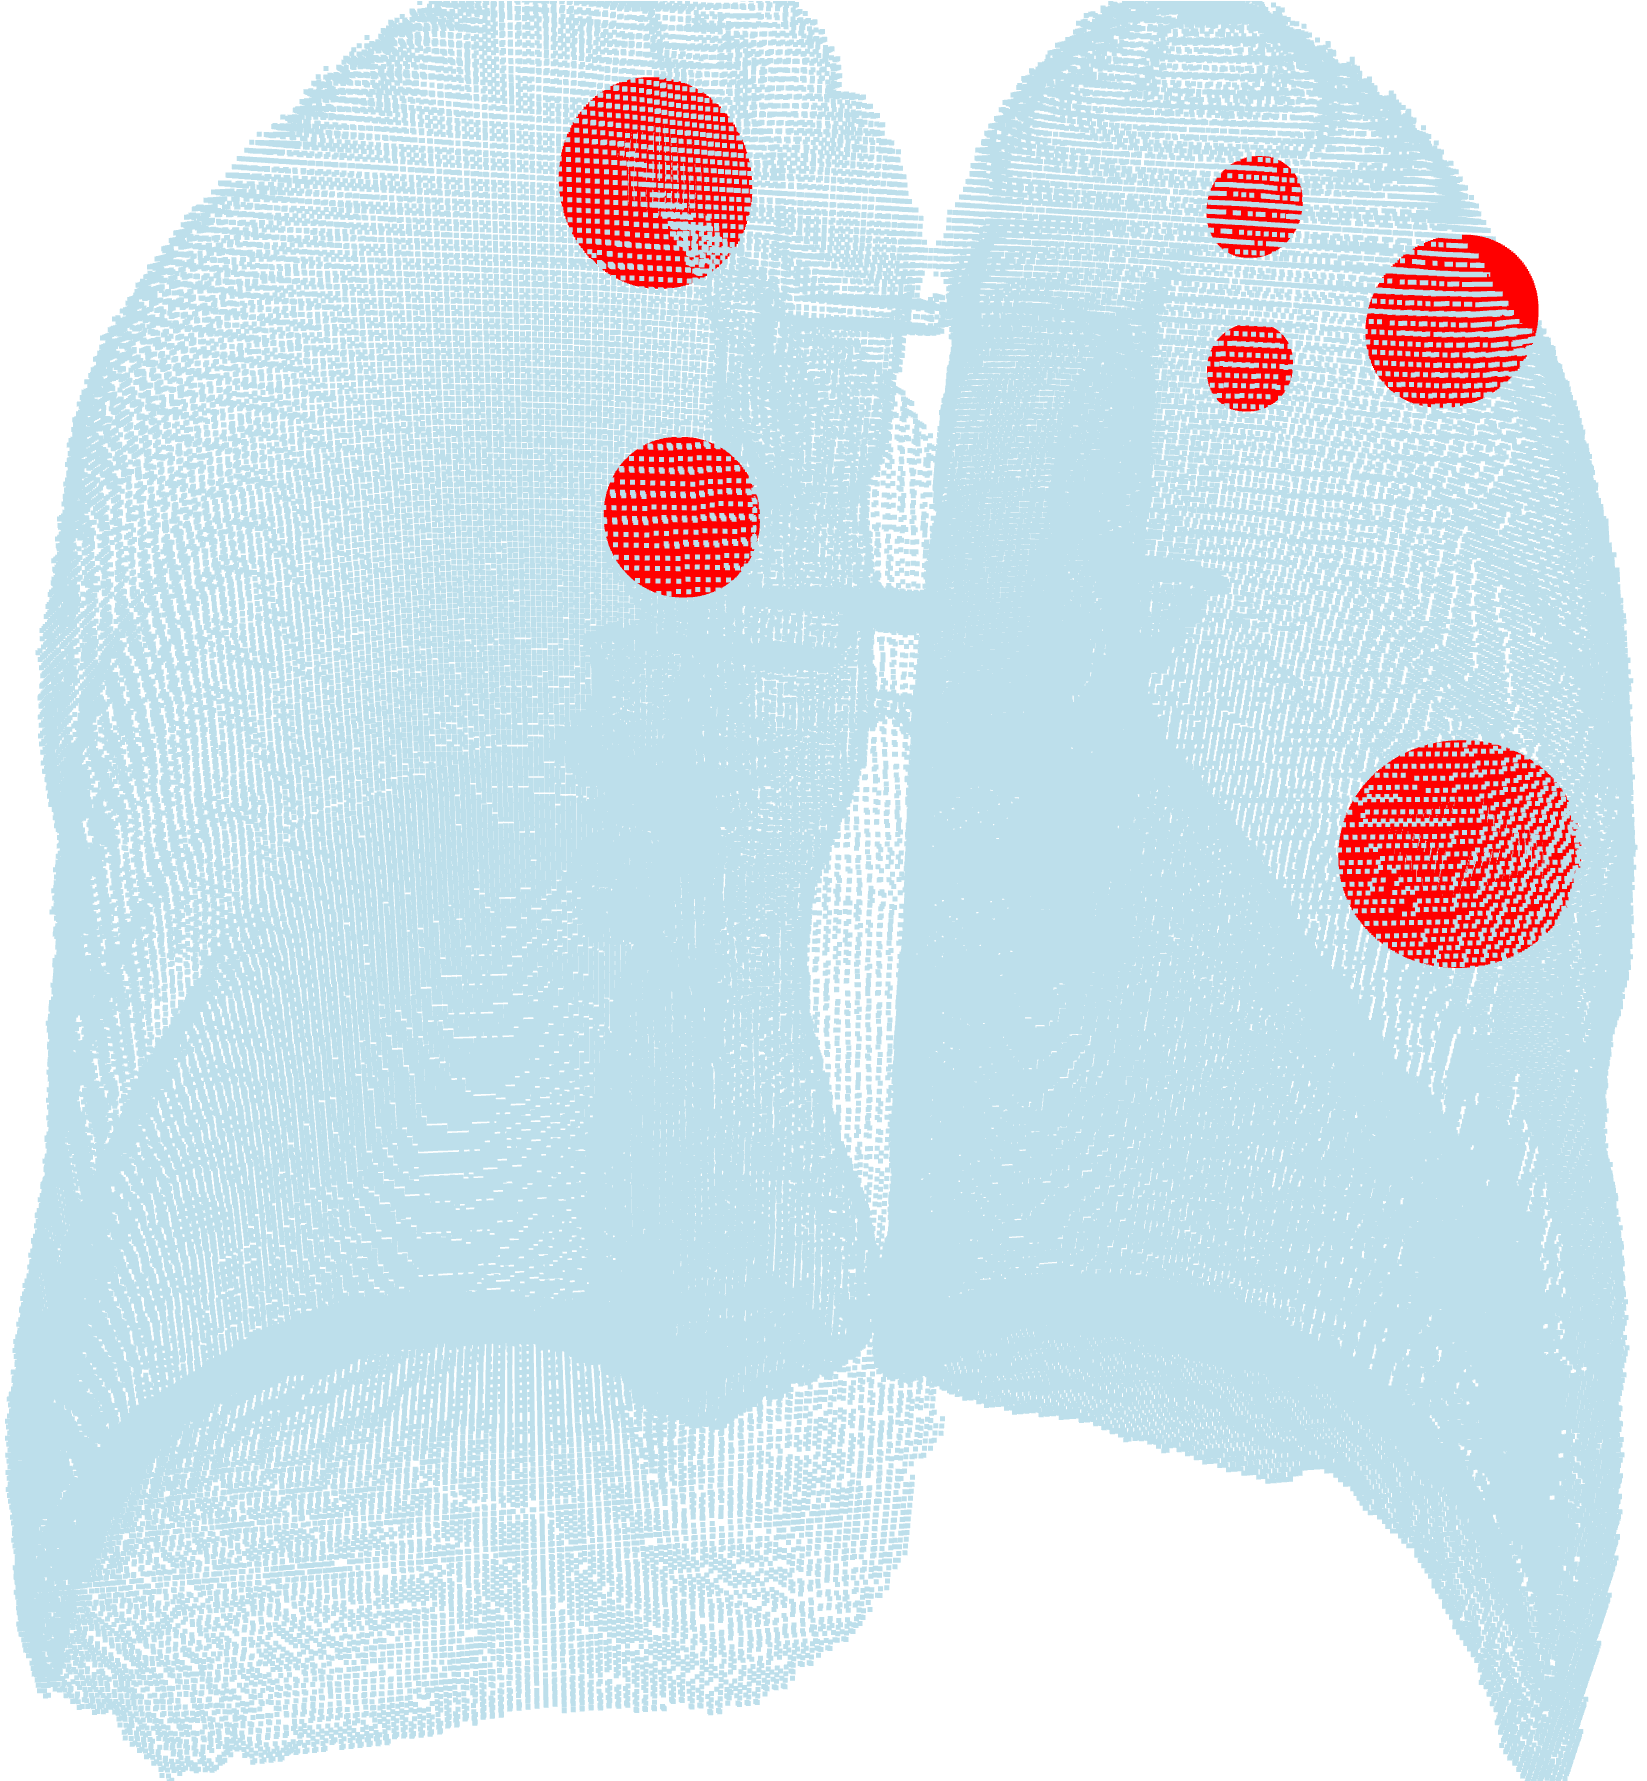

Case Study 1: Pulmonary Nodule Detection & Attribute Classification

The detection and attribute classification of the pulmonary nodule is a common medical image analysis task and is important for lung cancer diagnosis and clinical treatment. In this case study, we employ the “deep lung”-based neural network, proposed in [77], to detect and classify the pulmonary nodule.

The LUNA 16 dataset, which is based on the LIDC-IDRI dataset, [78], is used to train the model. The details of this case study are provided in the following subsections.

“Visualization” employs point cloud-based nodule visualization to display the pulmonary nodule detected by the 3D mask RCNN, and the loss visualization can visualize the training loss of the model.

VI-3 Result and Visualization

We train the 3D mask RCNN model and the 3D dual-path net with the training set and test them with the testing set. Fig. 8, which is rendered via the 3D point cloud, shows the result of the 3D mask RCNN. Fig. 9 presents the training loss of the 3D dual-path net. The left plot shows the total loss, while the right plot presents the loss for every classifier.